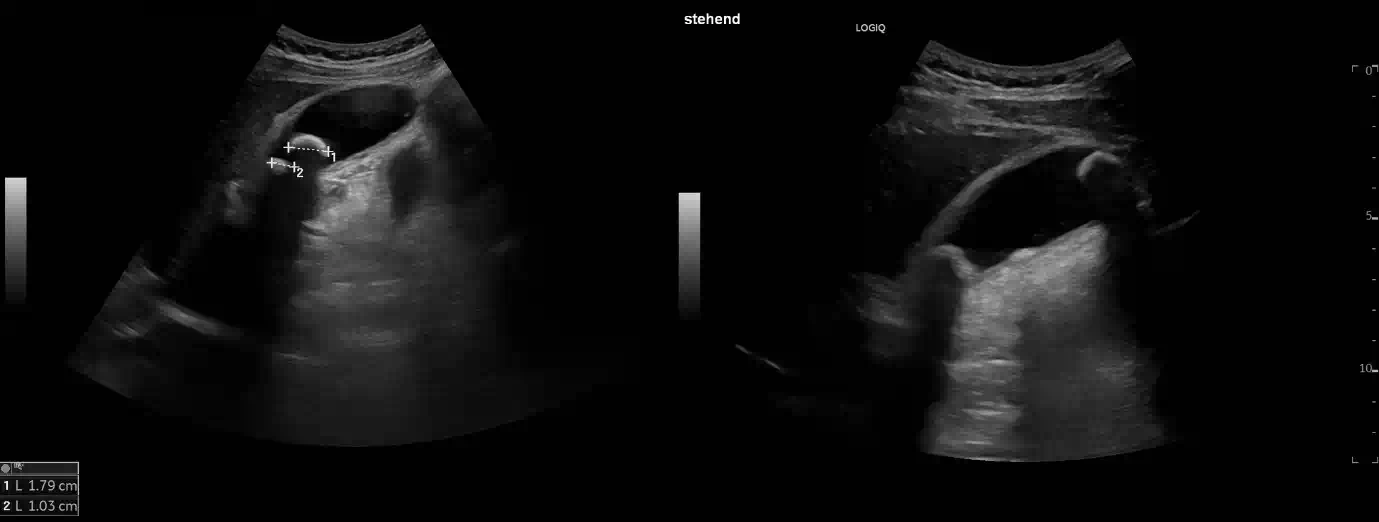

Im Längsschnitt über die Gallenblase erkennt man auf dem linken Bild neben einer verdickten Gallenblasenwand zwei Konkremente, die sich am Ausgang der Gallenblase, dem sogenannten Infundibulum (lat. Trichter), befinden. Lässt man den Patienten aufstehen, wie rechts im Bild dargestellt, fällt eines der Konkremente der Schwerkraft folgend in den Fundus der Gallenblase, während das zweite weiterhin im Infundibulum eingeklemmt bleibt.

Mit fortschreitender Druckerhöhung wird schließlich auch der arterielle Perfusionsdruck erreicht, wodurch auch die Arterien komprimiert werden. Ab diesem kritischen Punkt ist die Gallenblase vollständig von der Blutversorgung abgeschnitten und es entwickelt sich eine ischämische Nekrose der Gallenblasenwand. Unbehandelt kann dies zu Perforation, Peritonitis und septischen Komplikationen führen, weshalb die frühzeitige sonographische Diagnose und rechtzeitige Intervention von entscheidender Bedeutung sind. Die dargestellte fehlende Lageänderung eines der Konkremente bei Positionswechsel ist daher ein wichtiges diagnostisches Zeichen zum Beweis einer Obstruktion des Infundibulums